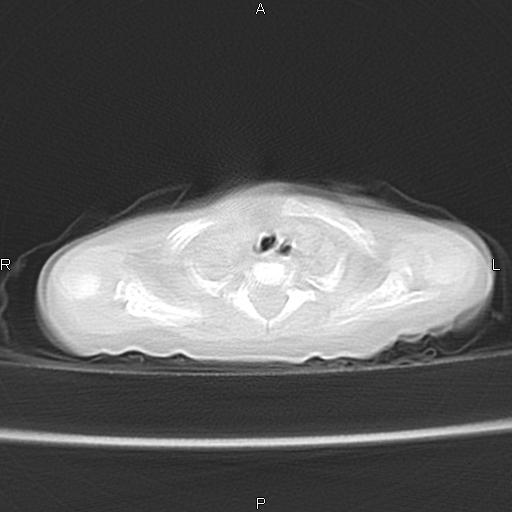

以下是引用aa13877358820在2010-7-26 12:35:00的发言:[br]男性,三个月,卧位胸片,咳嗽、气促、发热14天,两肺闻及细小水泡音。[br]